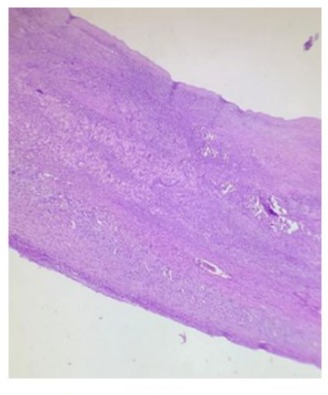

Figure 4: spleen tissue 10 x

Connective tissue wall with collagenized areas as well as sparse remnants of splenic tissue and areas of coagulative necrosis with simple flat epithelium

Pathology images by Dra. Maria Elena Murguia Bañuelos